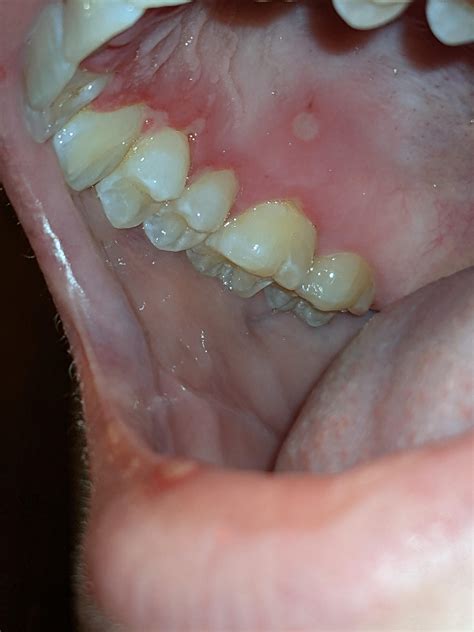

In many cases, the interplay between herpes and gums is characterized by a sudden onset of symptoms. Unlike a standard canker sore, which usually appears as a single ulcer on the soft tissue inside the cheek, herpetic lesions often appear in clusters. When these clusters develop along the gumline, they can make routine hygiene like brushing extremely painful, leading to a temporary decline in oral health if not managed correctly.

• Sudden gum inflammation: Gums may appear bright red, swollen, and shiny.

• Small, fluid-filled blisters: These can rupture, forming small, painful ulcers on the gingiva.